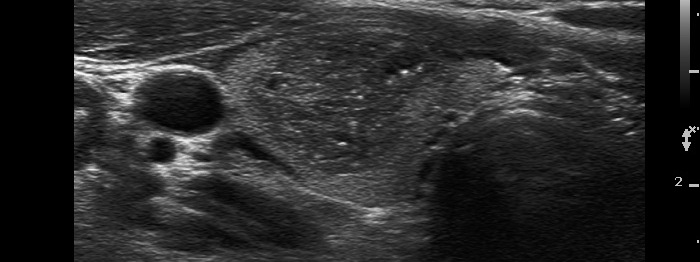

Papillary carcinoma (histological diagnosis) |

This case is less edifying or may be more edifying. Compared with the previous case, the granules here are less bright. Nevertheless, great proportion of them belong to punctate echogenic foci (arrows). It is worth to compare these with non-specific granules (arrowheads). |